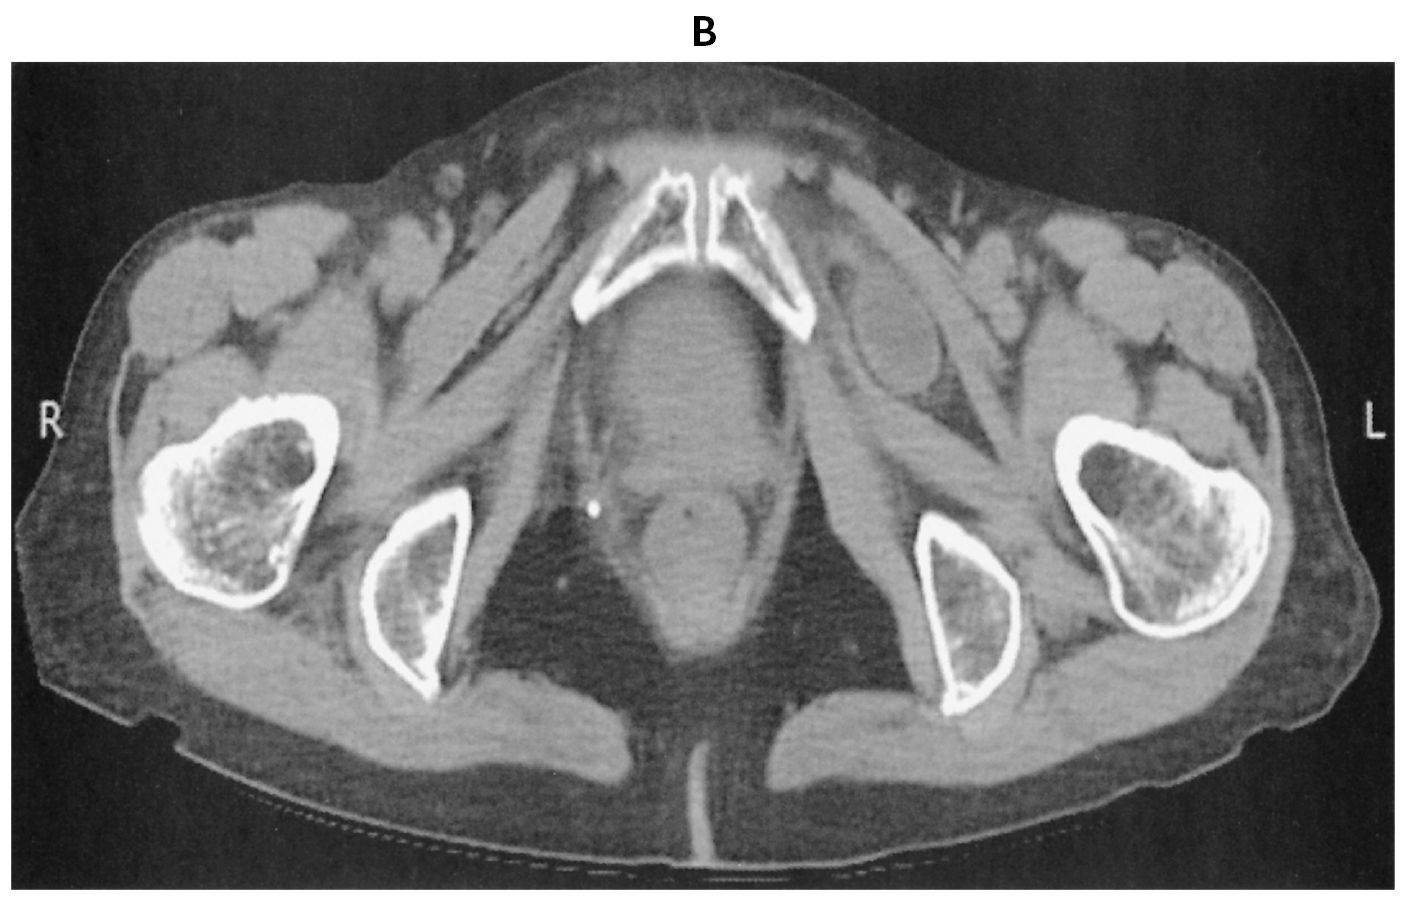

75歳の女性。腹痛と嘔吐を主訴に来院した。2日前から排便と排ガスがなく,徐々に腹部膨満が出現してきた。今朝から腹痛と嘔吐が出現したため受診した。既往歴は骨粗鬆症で治療中である。3年前に子宮筋腫で子宮全摘術を受けた。喫煙は20本/日を30年間。飲酒は日本酒1合/日を30年間。意識は清明。身長160cm,体重75kg。体温36.9℃。脈拍112/分,整。血圧148/74mmHg。SpO2 97%(room air)。①腹部膨隆を認める②腹部全体に軽度の圧痛を認めるが,③反跳痛を認めない④筋性防御を認めない⑤左股関節の伸展,外転により下肢の痛みやしびれを認める。直腸指診で異常を認めない。血液所見:赤血球410万,Hb 13.0g/dL,Ht 40%,白血球9,600,血小板27万。血液生化学所見:総蛋白6.4g/dL,アルブミン3.0g/dL,AST 25U/L,ALT 15U/L,尿素窒素35mg/dL,クレアチニン1.0mg/dL。CRP 2.5mg/dL。腹部単純CT(A)(B)を下に示す。

下線部のうち,この患者の腸閉塞の原因に特徴的な所見はどれか。